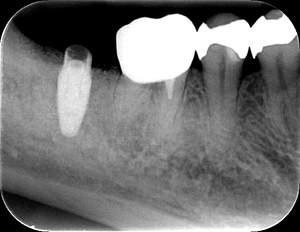

インプラント治療の症例10

レントゲン写真

- Before

- After

口腔内写真-1

口腔内写真-2

- 途中経過

| 年齢 | 40代・女性 |

|---|---|

| 主訴 | 左下6 |

| 治療内容 | インプラント埋入 |

| 治療費 | インプラント埋入料 440,000円 GBR(骨造成) 110,000円 サージカルガイド 55,000円 2次OPE 22,000円 静脈内鎮静麻酔 77,000円 合計 704,000円 (2023年5月現在) |

| 治療期間 | 7ヶ月 |

| リスク・副作用 | リスク・副作用 |

| 治療方針 | 左下6は歯根破折のため抜歯を行い、骨造成を同時に行いました。 骨ができてからインプラント埋入を行いました。 |

| 特記事項 | インプラントは人工物なので虫歯になることはありませんが、歯周病(インプラント周囲炎)にはなります。 インプラントを長持ちさせるには、毎日の歯磨きと合わせて、3~6ヶ月ごとの定期検診でのクリーニングが大切です。 |

| 担当者所見 | 歯を失ったまま放置してしまうと、周囲の歯に負担がかかるため、お口の中全体のバランスが崩れます。 インプラントは、骨に人工の歯根を埋め、被せ物を被せる治療法です。 外科的な手術が必要ですが、健康な歯を削ることなく、天然の歯と同じようにかめるようになります。 |